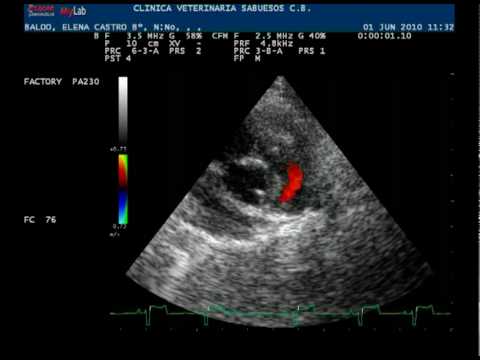

La ecocardiografía/Doppler es el estudio diagnóstico más indicado en casos de estenosis de la válvula pulmonar. Este examen permite obtener información detallada sobre la estructura y función de la válvula, así como sobre el flujo sanguíneo a través de ella.

Durante la ecocardiografía, se pueden observar imágenes en tiempo real del corazón utilizando ondas sonoras de alta frecuencia. Esto permite evaluar la forma y apariencia de la válvula pulmonar, y distinguir entre una válvula abombada y una válvula displásica (con anomalías estructurales). Esta distinción es importante porque las válvulas displásicas pueden requerir un enfoque de tratamiento diferente.

Además, la ecocardiografía proporciona mediciones precisas de los gradientes de presión a uno y otro lado de la válvula pulmonar. El gradiente de presión es la diferencia de presión entre las dos áreas a ambos lados de la válvula. Estos valores son útiles para determinar el grado de estenosis de la válvula pulmonar. Por lo general, se considera una estenosis leve si el gradiente máximo medido por ecocardiografía/Doppler es inferior a 30 mmHg. La estenosis se considera moderada si el gradiente máximo se encuentra entre 30 mmHg y 60 mmHg, y se considera de mayor intensidad si el gradiente máximo es superior a 60 mmHg o si el gradiente medio es superior a 40 mmHg.

Además de evaluar la estenosis de la válvula pulmonar, la ecocardiografía también puede proporcionar información sobre la presencia de obstrucción subvalvular (estrechamiento debajo de la válvula) y la presencia o ausencia de insuficiencia de las válvulas tricúspide o pulmonar (filtración de sangre en dirección opuesta).